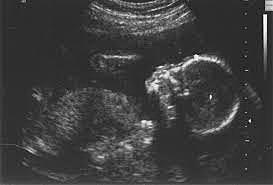

• An Ultrasound-In the womb

An Ultrasound-In the womb

My mother went to an ultrasound, which is something that sends high-frequency sound waves to the uterus to show a picture of the baby in the womb (2.7 of textbook).At first she wanted a boy because she was always so much of a tom boy and the first ultrasound showed that I was a girl.Studies have shown that looking at the ultrasound does help with the feeling of attachment (2.7 of textbook) which is probably why the constant monitoring of my growth helped my mother grow to love me even more.